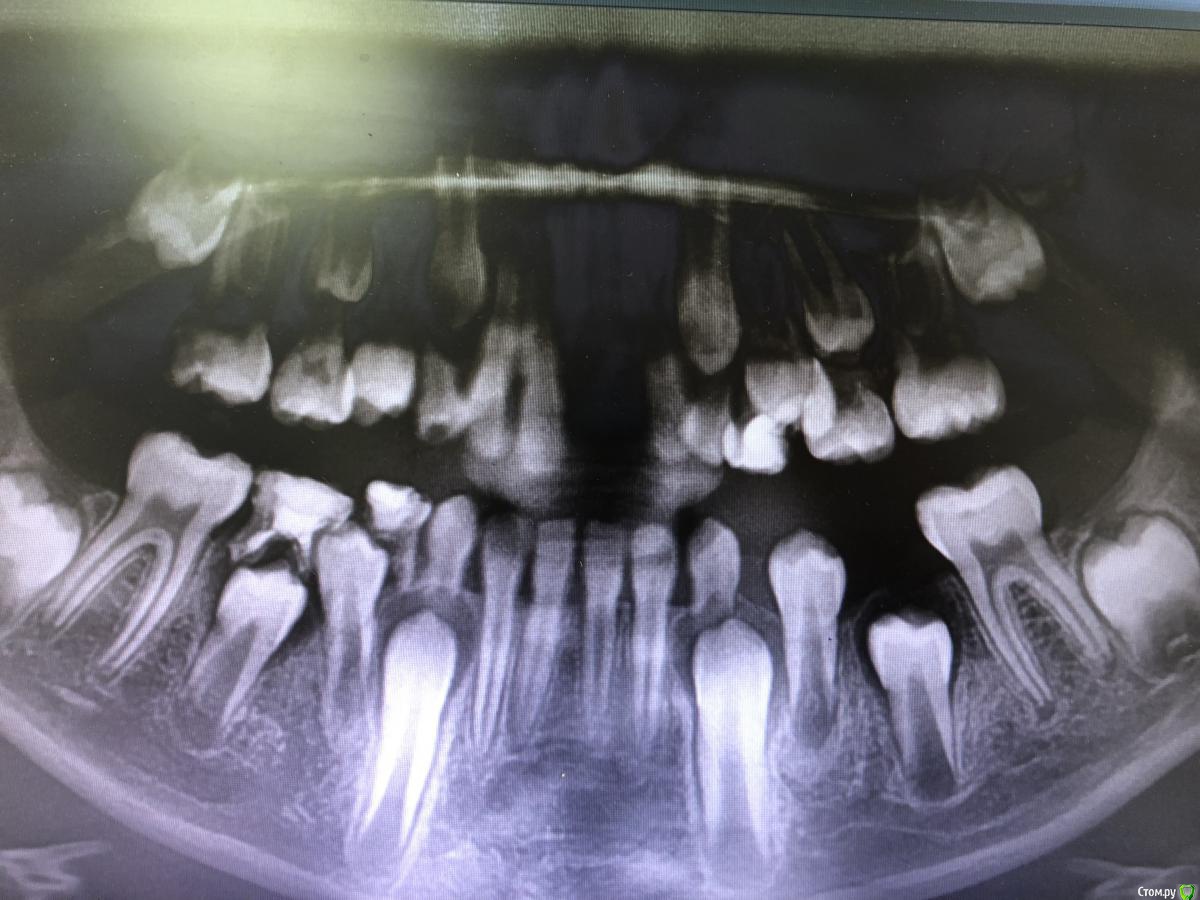

dashkovski Опубликовано 24 августа, 2018 Поделиться Опубликовано 24 августа, 2018 (изменено) Дорогие коллеги! Подскажите что делать. Пришёл мальчик 10 лет, 4 июля произошёл перелом и вколоченный вывих 21 зуба. Они обратились в одну из клиник нашего города, там им сделали ОПГ и почему то реплантацию сразу не провели, а поставили частичную брекет систему и приклеили кнопку на вколоченный зуб, при этом дугу поставили очень слабую 014NiTi . Спустя месяц они пришли ко мне на приём, решив что в той клинике им ни чем не помогли. Я поменяла дугу на более жесткую 16\22 NiTi, но спустя 3 недели никаких изменений не произошло, разве что соседние зубы начали подниматься, по снимку передний отдел виден не четко, но все же. И похоже на развивающийся периодонтит. Есть ли смысл сейчас реплантировать зуб и депульпировать и протезировать? Хотелось бы его сохранить до 18 лет Изменено 24 августа, 2018 пользователем dashkovski Ссылка на комментарий

dashkovski Опубликовано 24 августа, 2018 Автор Поделиться Опубликовано 24 августа, 2018 ЭОД никто не делал, скорее всего там и пульпит и периодонтит и анкилоз уже, потому как такие зубы обычно за 1-2 дня вытягиваются. Отечность десны есть, но без выделений. 1 Ссылка на комментарий

red_butler Опубликовано 25 августа, 2018 Поделиться Опубликовано 25 августа, 2018 Коллеги, я смотрел этого пациента. Зуб вколочен полностью, слизистая спокойная, отделяемого нет, на рвг перелом коронарной части на 1/2, эод провести не возможно. Снимок смогу прикрепить в понедельник 2 Ссылка на комментарий

Джима Опубликовано 28 августа, 2018 Поделиться Опубликовано 28 августа, 2018 анкилоз 100%, я бы делала эндо с мта, потом кт - найти зоны анкилоза, потом можно попробовать пьезотомом рассечь эти зоны и выставить зуб в нормальное положение, месяц в брекетах, пока новый анкилоз произойдет, потом реставрация. И сказать родителям, чтоб готовились к имплантации, это уже не зуб, а времянка(( 3 Ссылка на комментарий